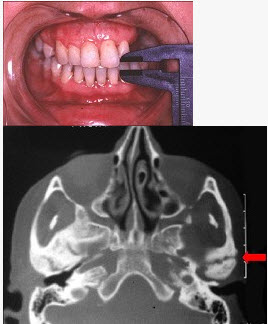

患儿,5岁,外伤后逐渐出现张口困难,咬合关系错乱,髁突动度减弱,外观及X线检查结果如图。最可能的诊断是()

E、颞下颌关节强直